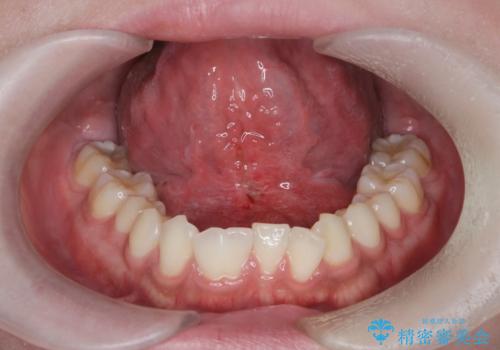

滑舌の改善 舌小帯の形成術

- 友人に滑舌の悪さを指摘され、改善を求めて来院されました。

舌下部に位置する小帯(ヒダ)の長い付着が認められるので、形成術を行うことで滑舌の改善を計画します。

小手術は5〜10分程度で終了します。